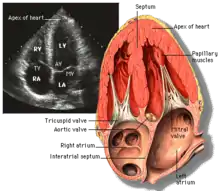

Transthoracic echocardiography (TTE) uses ultrasonic waves for continuous heart chamber and blood movement visualization. It is the most commonly used imaging tool for diagnosing heart problems, as it allows non-invasive visualization of the heart and the blood flow through the heart, using a technique known as Doppler.

TTE is commonly used to evaluate patients with coronary artery disease.[4] Stress echocardiography is used to diagnose coronary artery disease and assess myocardial viability.[4]